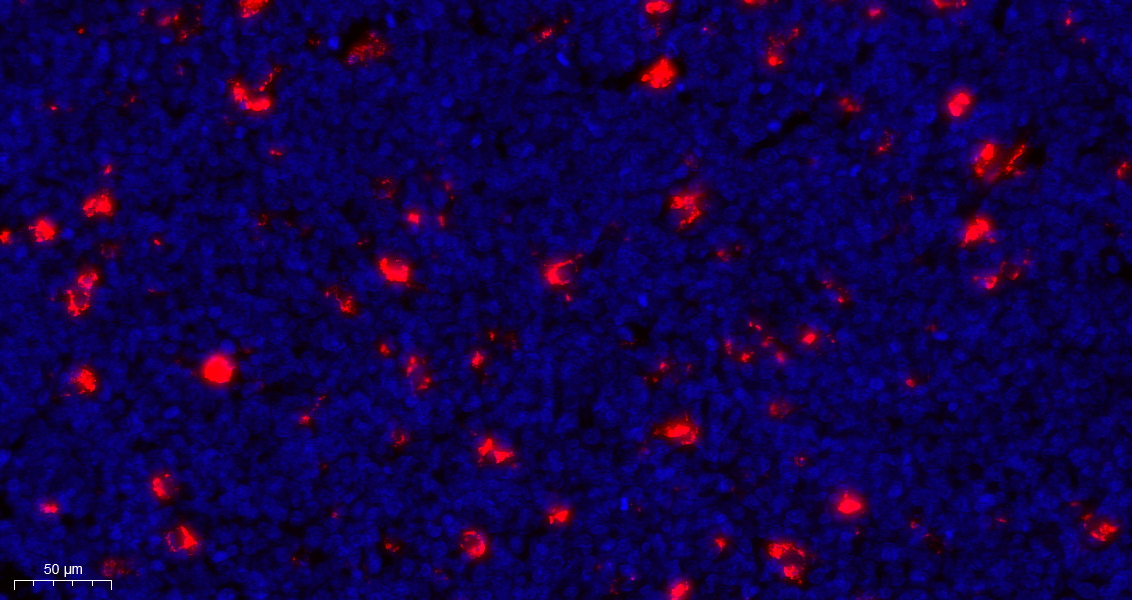

CD68 (AB1512) mouse mAb

Application:Immunohistochemistry (IHC)

CD68 is a glycoprotein with a molecular weight of about 110 kDa, which is located in the cytoplasm. It is expressed in monocytes, macrophages, histiocytes, large lymphocytes and osteoclasts. CD68 is mainly used to label macrophages, histiocytes and their tumors. Clinically, it is used to diagnose fibrous histiocytoma, histiocytosis and other diseases with rich histiocytes.

Immunohistochemistry (IHC)

IHC, 1:50-1:200